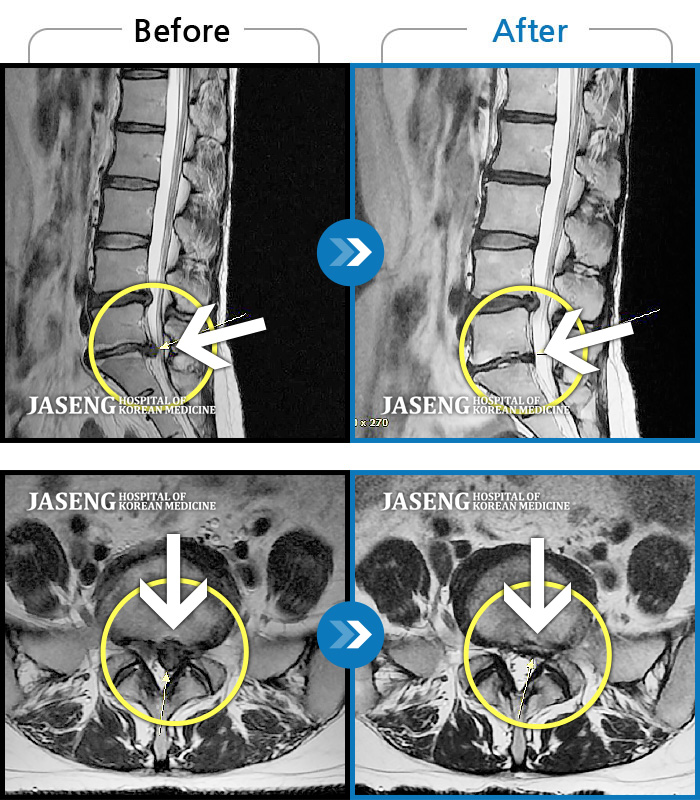

허리디스크

울산 · 정운석 원장

좌측 하지 외측이 저리면서 당김증상 및 감각둔화

촬영시기

2016.12.22 ~ 2022.11.24

2022.12.09